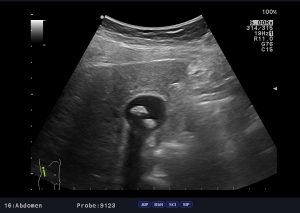

Sonographie

Die Sonografie ist ein bildgebendes Verfahren, bei dem die inneren Organe mit Ultraschall dargestellt werden. Sie wird sowohl zur Diagnose von Erkrankungen, als auch zur Verlaufskontrolle angewandt.

Mit ihrer Hilfe können verschiedene Bauchorgane beurteilt werden, z. B. die Leber, die Gallenblase, die Gallengänge, die Bauchspeicheldrüse, die Bauchschlagader, die Nieren, die Milz und der Darm. Durch das Drehen und Kippen des Schallkopfs können die einzelnen Organe in verschiedenen Ebenen dargestellt werden. Die Untersuchung ist schmerzfrei und ohne spezielle Vorbereitung möglich. Für die Diagnostik einiger Bauchorgane wie zum Beispiel der Gallenblase oder der Bauchspeicheldrüse, ist es allerdings vorteilhaft, wenn der Patient nüchtern ist.